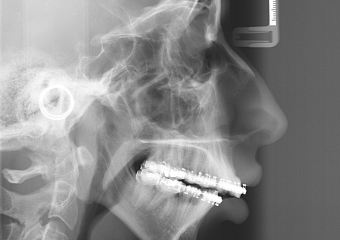

Raio x inicial